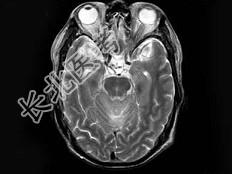

- 单项选择题男,55岁, 头痛40余天,呕吐2天伴共济失调。化验检查: 脑脊液蛋白:2006mg/l, 细胞数60个/mm3MRI平扫显示不佳,增强扫描后见脑膜强化及脑内小结节状强化以脑膜强化为明显, 据此最可能的诊断为 ( )